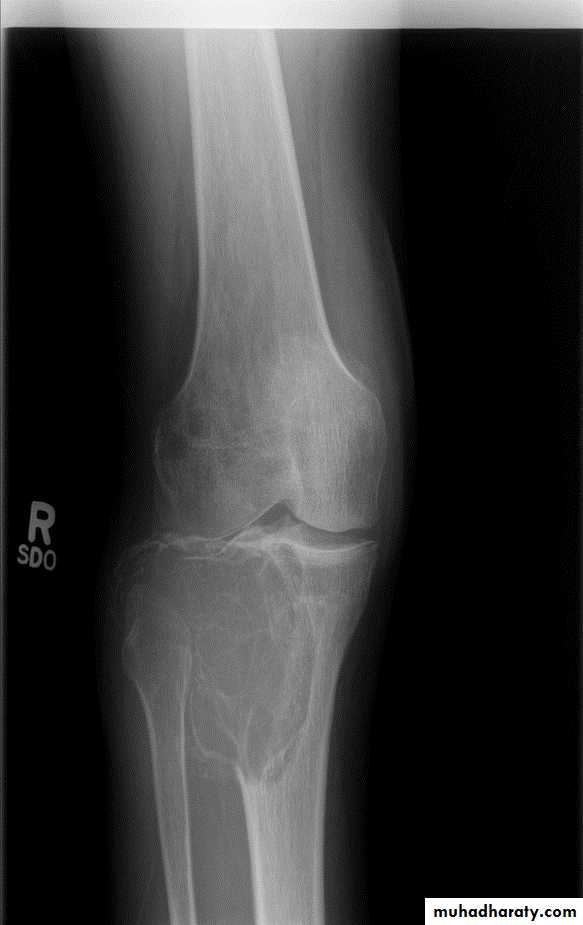

Area of bone destruction or sclerosis with ill-defined margins, wide zone of transition & periosteal reaction with or without cortical destruction & soft tissue swelling.Osteosarcoma :

Age: 5-20-yrs, elderly with Paget's disease.Site: metaphyseal around the knee joint.

Findings:

Lytic

Blastic

Mixed

Poorly defined bony destruction.

Sun ray speculation (periosteal reaction).

Elevation of the periosteum at the margin producing the so called Codman's triangle.

Cortical destruction.

Soft tissue swelling.